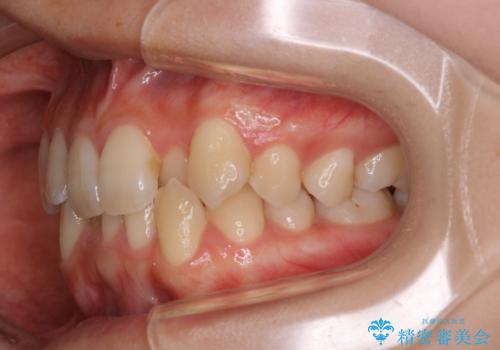

下顎前歯の先天欠損と上顎前歯のクロスバイト:インビザライン治療

- 上の前歯が1本後ろに入ってしまっていることが気になるとご相談にいらした方です。

元々下の前歯が1本欠損しており、上下の噛み合わせや、歯のサイズバランスを考慮しながら治療を行いました。

クロスバイトしている歯が深く噛み込んでおり、この歯を外に出してくる際に強い咬合力が加わると歯が失活する恐れがあることを説明し、合わせて咬筋へのボトックス注入を行いました。

下顎切歯が1本欠損しているため、上顎前歯部を少しずつストリッピングして、上下の噛み合わせ、バランスの向上を図りました。